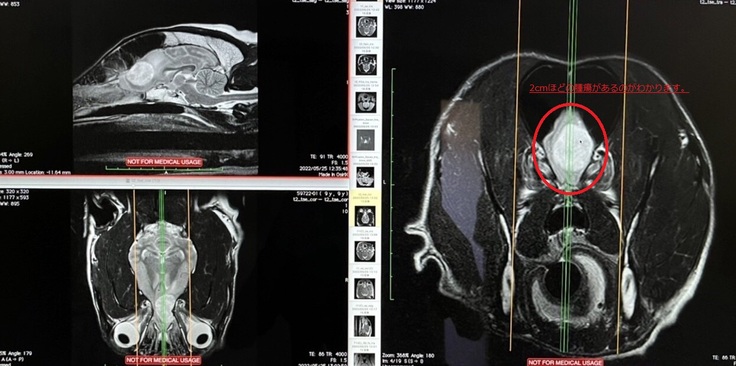

総合病院でMRIをして頂いたところ、みるくの脳に2センチぐらいの腫瘍があることがわかりました。

手術をしないと、余命半年と言われ、この腫瘍が大きくなれば、脳を圧迫して、痛みが出たり、脳障害が出る可能性があるということでした。

◆診断書

(動物病院名は伏せさせて頂きます。動物病院から掲載許可を得ています。)